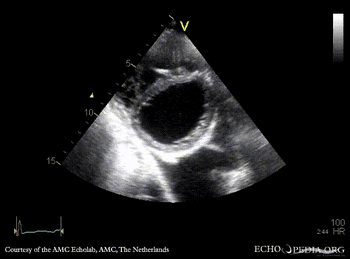

E00450.gif E00451.gif

PLAX: prolaps of PMVL, huge amount of pleural effusion PLAX: Color Doppler, severe mitral regurgitation, excentric jet